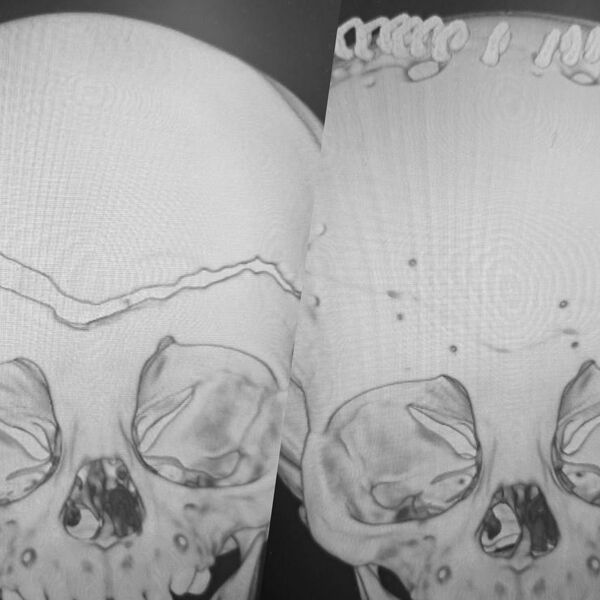

«У ребенка была гигантская эпидуральная гематома и линейный перелом лобной и теменной костей с расхождением линии перелома до 1,5 см», — рассказал заведующий нейрохирургическим отделением ВКБ №2 Сергей Моисеенко, добавив, что у его коллега на счету была каждая минута.